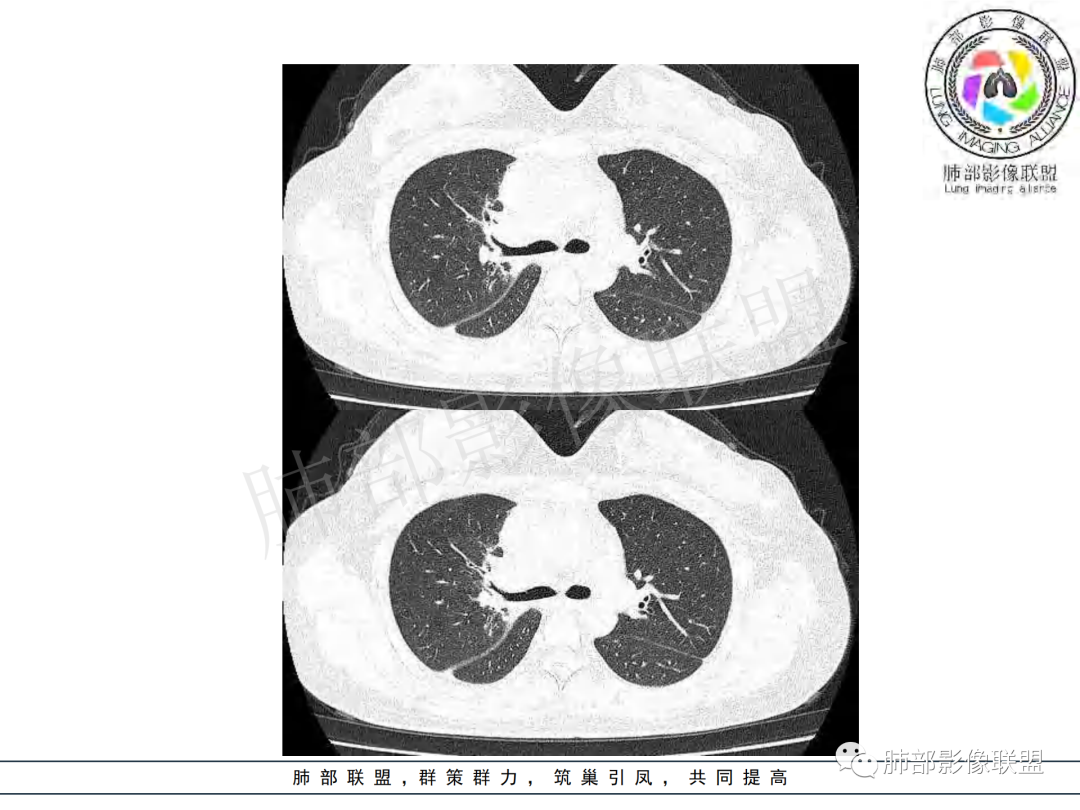

右肺肺门旁肿块,右肺中间段支气管腔内结节,增强强化不均;纵隔多发淋巴结环形强化,右侧少量胸腔积液,临床发热入院,考虑结核,鉴别肿瘤。

右肺门增大,远端花花草草不明显,支气管管壁增厚,纵隔淋巴结环形强化,年龄,病程,考虑炎性病变,结核可能,有个层面支气管截断,有强化,鉴别粘表。

女,20,病程长达8月,发热、胸痛、右侧胸腔积液病史。胸部CT:右肺门旁不规则肿块影,右中间支气管腔内结节,纵隔多发淋巴结肿大;强化不均匀,灶性坏死灶,环形强化;右侧少量胸腔积液并局部肉芽肿样突起。年轻女性,长病程,多部位,考虑慢性炎症,结核?鉴别肿瘤。

青年,右肺门增大,见软组织肿块影,部分支气管腔结节,并管腔狭窄,增强后明显不均匀强化,伴纵隔多发肿大淋巴结,环形强化,考虑恶性,类癌,鉴别支气管内膜结核

右肺门不规则肿块,向气管腔内生长,不均匀强化,其内粘液栓,纵隔淋巴结增大,部分有坏死,胸膜结节强化,考虑恶性,粘表?类癌?鉴别结核

右肺肺门旁肿块,右肺中间段支气管腔内结节,增强强化不均;纵隔多发淋巴结环形强化,右侧少量胸腔积液,考虑结核可能,鉴别肿瘤。

年轻女性,慢性病程,发热、胸痛。右肺门旁不规则肿块影,纵隔多发淋巴结肿大;强化不均匀,环形强化;右侧少量胸腔积液;首先考虑结核,鉴别肿瘤,结节病。

女性,20岁。高热、畏寒。右肺上叶近肺门区不规则肿块,周围斑点、片小结节影伴肿大淋巴结,肿块包绕并突入右主支气管腔内,增强后肿块不均匀强化,淋巴结环形强化中心低密度,考虑结核。

本例患者,年轻女性,慢性病程,多次抗感染治疗效果不佳,实验室检查示白细胞及中性粒细胞不高,不支持普通细菌感染,虽然肺泡灌洗液X-Pert检测阴性,结合患者胸部CT结核感染亦不能排除,胸部CT主要表现为右侧肺门及纵隔淋巴结肿大,仔细观察不难发现右中间支气管内新生物凸向管腔内,增强扫描,右肺门(10R)及纵隔淋巴结(2R,4R)明显不均匀强化,内部呈不规则低密度无强化区,被周边高强化区包绕(环形强化)的特点,首先应当想到纵隔淋巴结结核诊断。淋巴结分布亦不符合肺部恶性肿瘤迁徙途径。